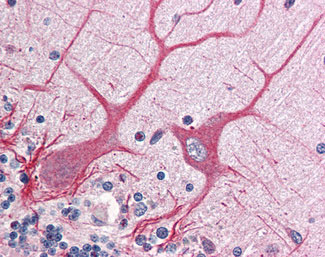

Anti-NOTCH1 antibody IHC of human brain, cerebellum. |